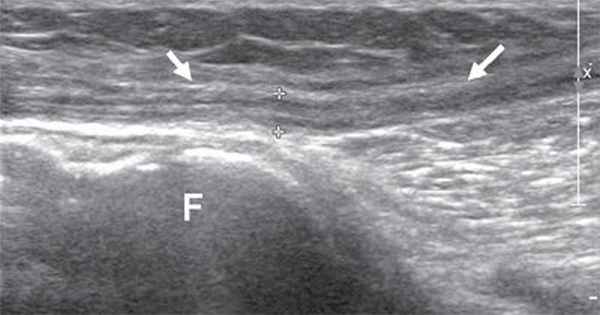

Общий малоберцовый нерв, отделившись от основного ствола, спускается латерально под двуглавой мышцей бедра к головке бедренной кости. В области головки малоберцовой кости нерв располагается поверхностно, прикрыт только фасцией и кожей, здесь он также хорошо доступен визуализации (рис. 5).

Рис. 5. Продольная сонограмма общего малоберцового нерва (стрелки) на уровне головки малоберцовой кости (F).

Далее общий малоберцовый нерв проникает в толщу проксимального отдела длинной малоберцовой мышцы и делится на две свои конечные ветви - поверхностный малоберцовый нерв и глубокий малоберцовый нерв. Визуализация конечных ветвей общего малоберцового нерва затруднена из-за их малого диаметра и отсутствия анатомических маркеров при их прохождении в толще мышц голени. Поверхностный малоберцовый нерв делится на конечные ветви (тыльные ветви стопы) на латеральной поверхности нижней трети голени. Глубокий малоберцовый нерв переходит на переднюю поверхность голени и здесь, располагаясь латерально, сопровождает передние малоберцовые сосуды. На тыл стопы нерв попадает под нижним удерживателем разгибателей и под сухожилием длинного разгибателя I пальца. Здесь он делится на концевые ветви. Для визуализации общего малоберцового нерва и его ветвей удобнее использовать датчики с частотой 9-17 МГц.